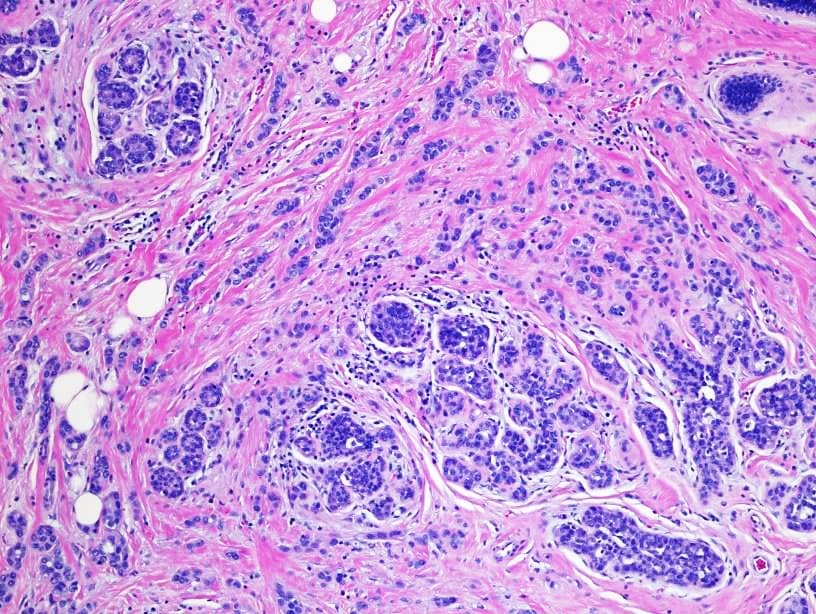

| Prue's Histology |

Image Source: Histopathology of invasive lobular carcinoma, next to lobular carcinoma in situ, Randi Ryan, Ossama Tawfik, Roy A Jensen, Shrikant Anant, Wikimedia Commons, permitted under CC BY 4.0. |